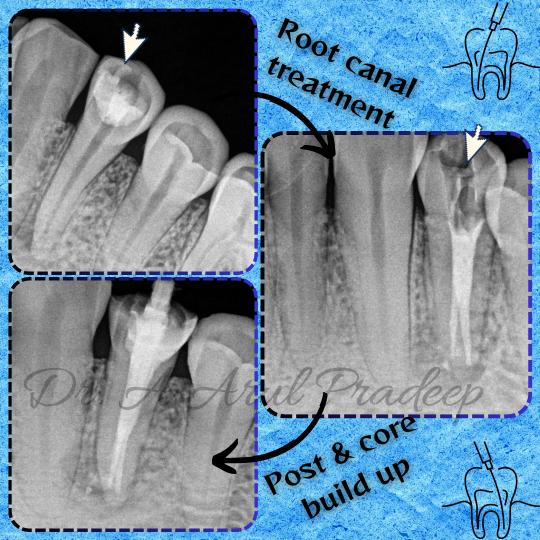

Root canal treatment in Craft32 dental care, salig...

Root canal treatment in Craft32 dental care saligr...